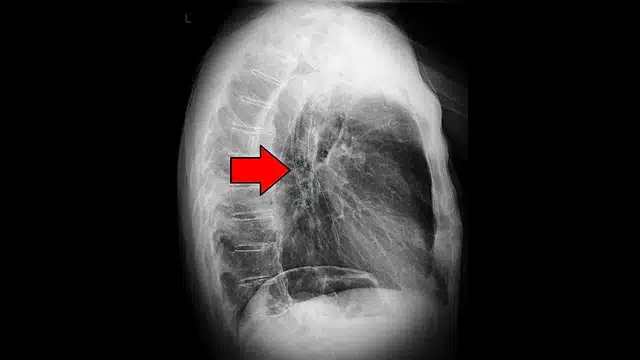

Αχαλασία οισοφάγου και καρκίνος: ποια είναι η σχέση;

Η αχαλασία είναι μια χρόνια διαταραχή της κινητικότητας του οισοφάγου που προκαλεί δυσκολία στην κατάποση και συχνά έντονη ανησυχία στους ασθενείς. Ένα από τα πιο φορτισμένα ερωτήματα είναι: «Μπορεί να εξελιχθεί σε καρκίνο;» Η απάντηση θέλει ακρίβεια: ναι, η αχαλασία συνδέεται με αυξημένο κίνδυνο καρκίνου του οισοφάγου, αλλά ο απόλυτος κίνδυνος για τον κάθε ασθενή παραμένει σχετικά χαμηλός και εξαρτάται πολύ από τη διάρκεια της νόσου, τους παράγοντες κινδύνου και την πορεία μετά τη θεραπεία. Αχαλασία οισοφάγου και καρκίνος – Ανάλυση.